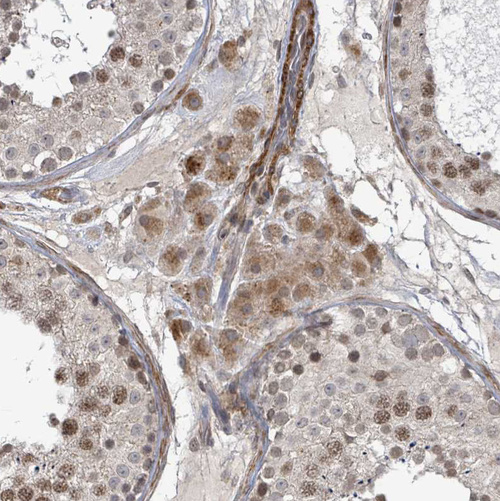

Immunohistochemical staining of human testis shows moderate cytoplasmic positivity in Leydig cells.